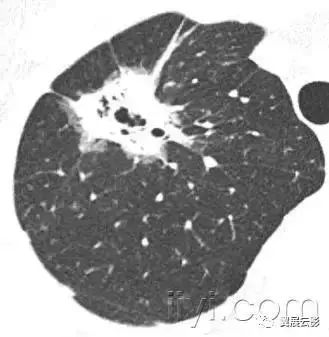

附图为小叶中心性肺气肿

小叶中心性异常包括(1)结节(2)树芽征,提示小气道病变(3)由于临近间质的增厚或者浸润导致小叶中心结果更加清晰(4)小叶中心性肺气肿导致的异常低密度。

CT:正常次级肺小叶中心的点状或者线状的密度增高影,胸膜下25px范围内最明显,代表小叶内的动脉,直径约1mm。

解剖:小叶中心性用于描述次级肺小叶的支气管血管束中心区域。病理学上也用这一术语描述终末小支气管远端,位于呼吸性细支气管和肺泡管中心的病变。